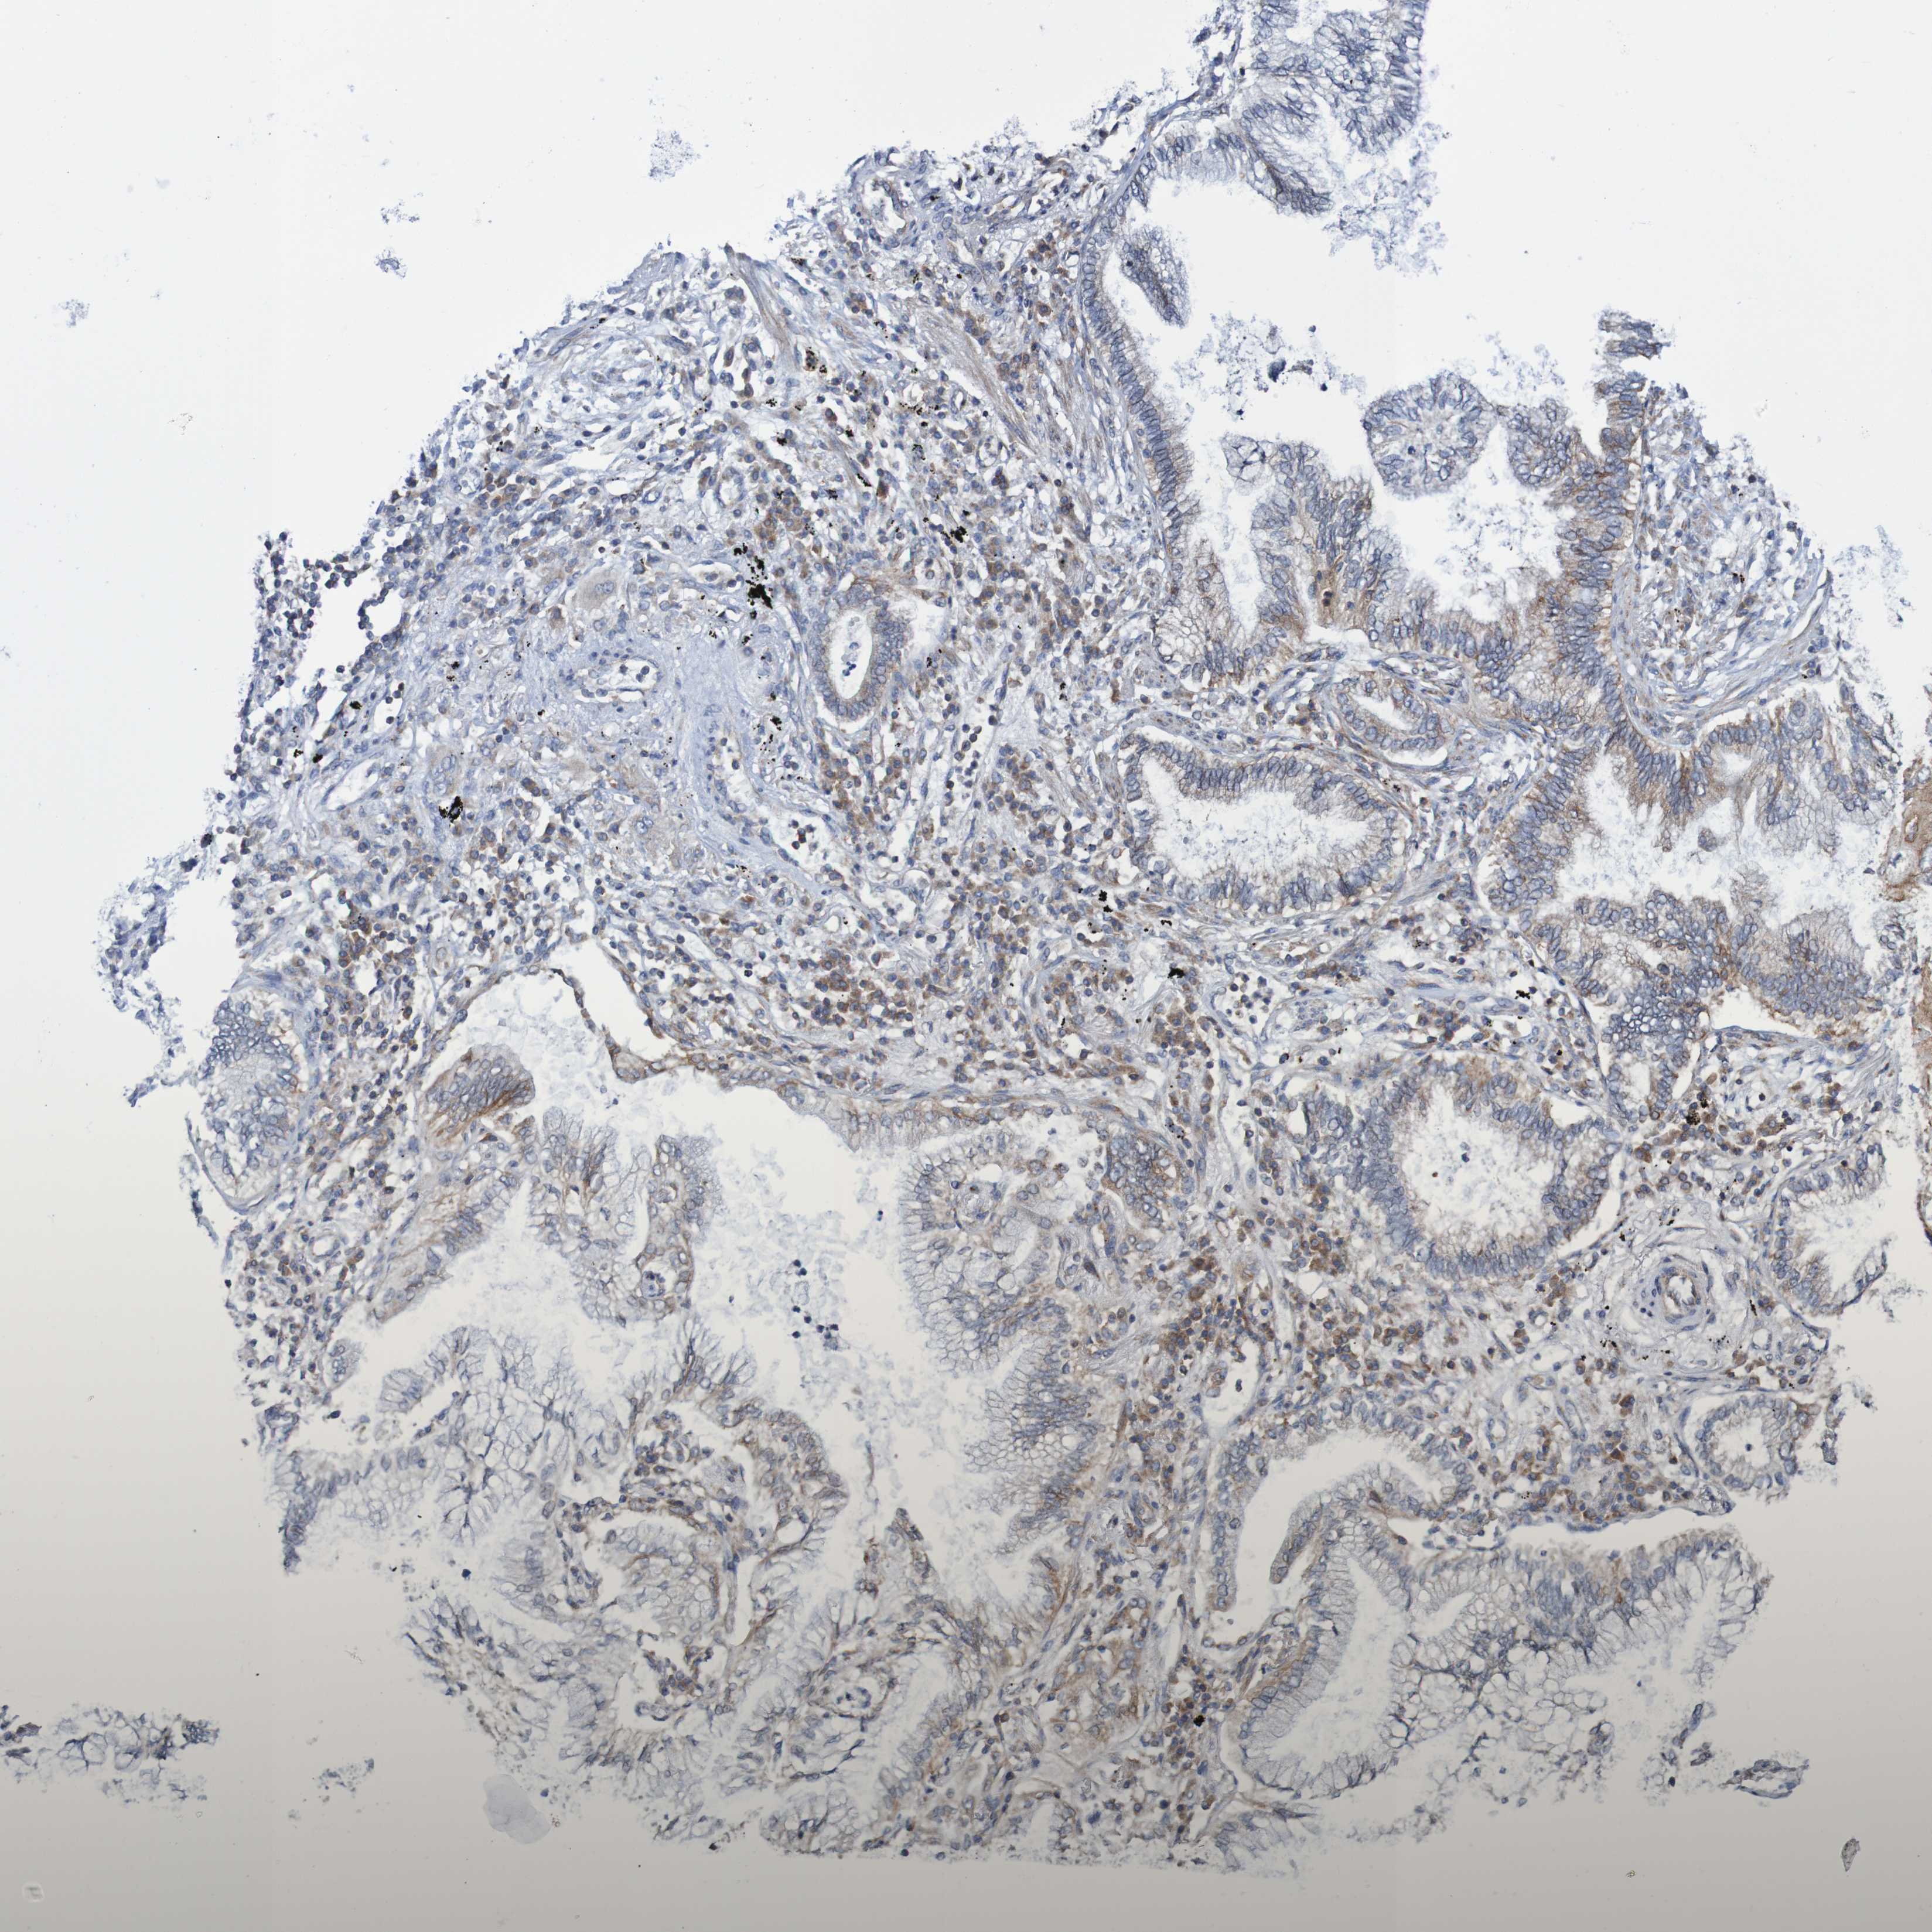

CANCER LUNG CANCER Show tissue menu

LUAD TCGA LUAD VALIDATION LUSC TCGA LUSC VALIDATION PROTEIN LUAD CPTAC PROTEIN LUSC CPTAC PROTEIN EXPRESSION

ANTIBODIES

AND

VALIDATION